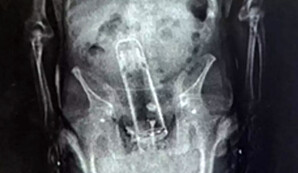

При стандартном рентгеновском осмотре сотрудники учреждения обнаружили в теле мужчины металлический предмет, который оказался термосом.Газета.Ru

По словам шерифа округа Полк Грейди Джаджа, "задержанный принес термос в тюрьму самым необычным способом".Газета.Ru